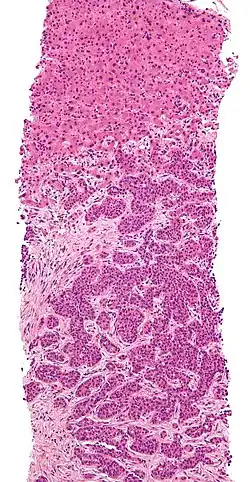

Biopsja wątroby

Biopsja wątroby – badanie medyczne, który wykonuje się w celu rozpoznania chorób wątroby, oceny stopnia zaawansowania chorób wątroby i monitorowania postępów leczenia[1].